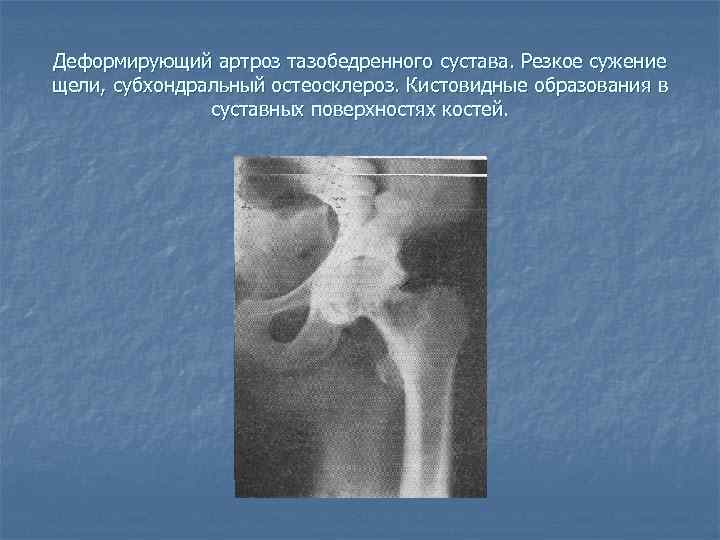

Рентгеновские снимки остеосклероза костной ткани